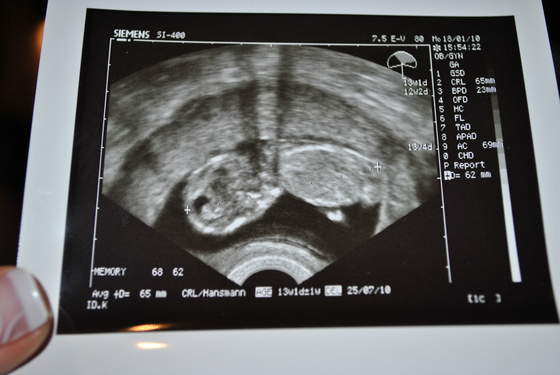

Dzidziolek rośnie ma 2,55 cm, co wg usg potwierdza 9w3d (wiec ciąża trochę młodsza ze względu na późną owulacje- termin zostawiam bez zmian bo i tak będzie sie zmieniał)Serduszko bije 163/min .